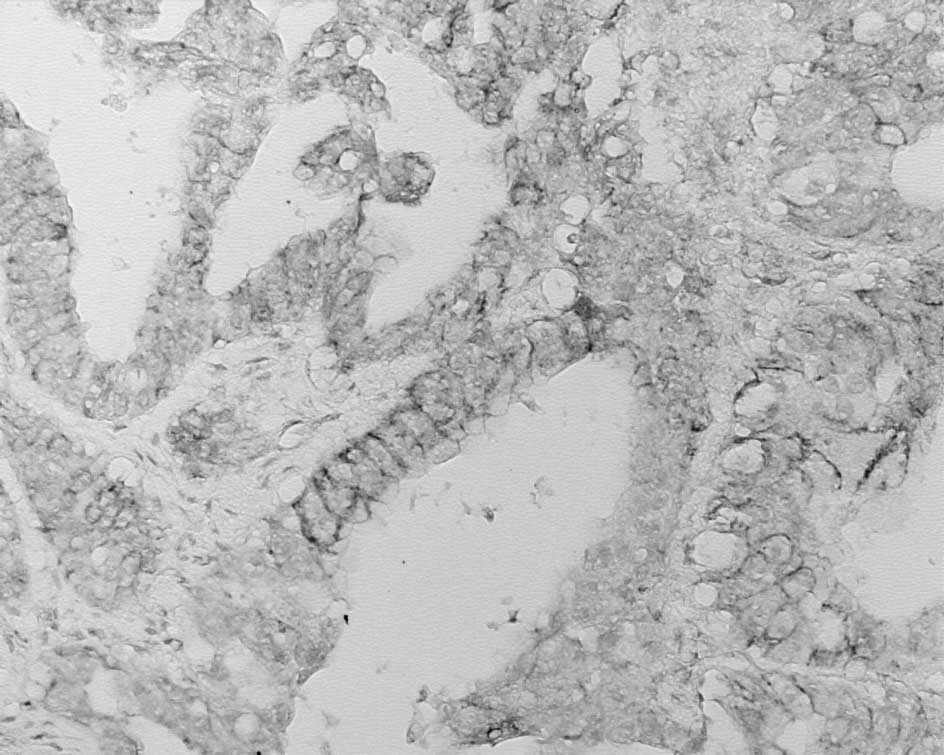

The gross appearance of the excised gallbladder with the monolocular large cyst is shown in Fig. 4. On the cut face of the gallbladder, the lumen was occupied by a solid neoplasm. The cyst included a large amount of serous fluid and protruded continuously from the body of the gallbladder, but was not part of the gallbladder lumen. Microscopic examination suggested that the internal wall of the cyst was covered with non-neoplastic low papillary columnar epithelium and papillary adenocarcinoma. However, the remainder of the cyst was composed of papillary carcinoma (Figs. 4B and 5A). A macroscopic solid mass observed in the gallbladder lumen also consisted microscopically of various-sized cystic components composed of papillary adenocarcinoma (Fig. 5B).

Figure 5

(A) The microscopic appearance of the cyst showed papillary adenocarcinoma similar to the gallbladder. (B) Cancer cells organized into various sized cystic structures in the gallbladder wall.

One of the possible mechanisms underlying the formation of these cysts is the occlusion of the communication between RAS or a blockage in the communication between the diverticulum and gallbladder due to inflammation or cancer growth. The present case showed large and small cancerous lesions forming various cystic structures, suggesting that the large cysts may have arisen following the transition from one of the small cysts in the solid gallbladder carcinoma (Fig. 5B). Therefore, we speculate that this characteristic papillary adenocarcinoma results in the formation of cysts.